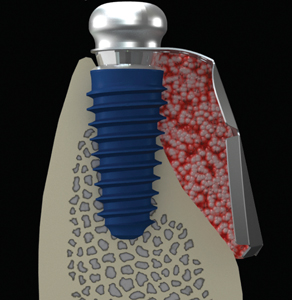

Dentsply Sirona’s integrated solutions for implant dentistry enable dental professionals to deliver safer and more efficient treatment processes as well as increased comfort and improved quality of life for their patients. The merger between DENTSPLY and Sirona has brought together two companies with long-term expertise in their respective fields, providing innovative and clinically tested technology, … Read more